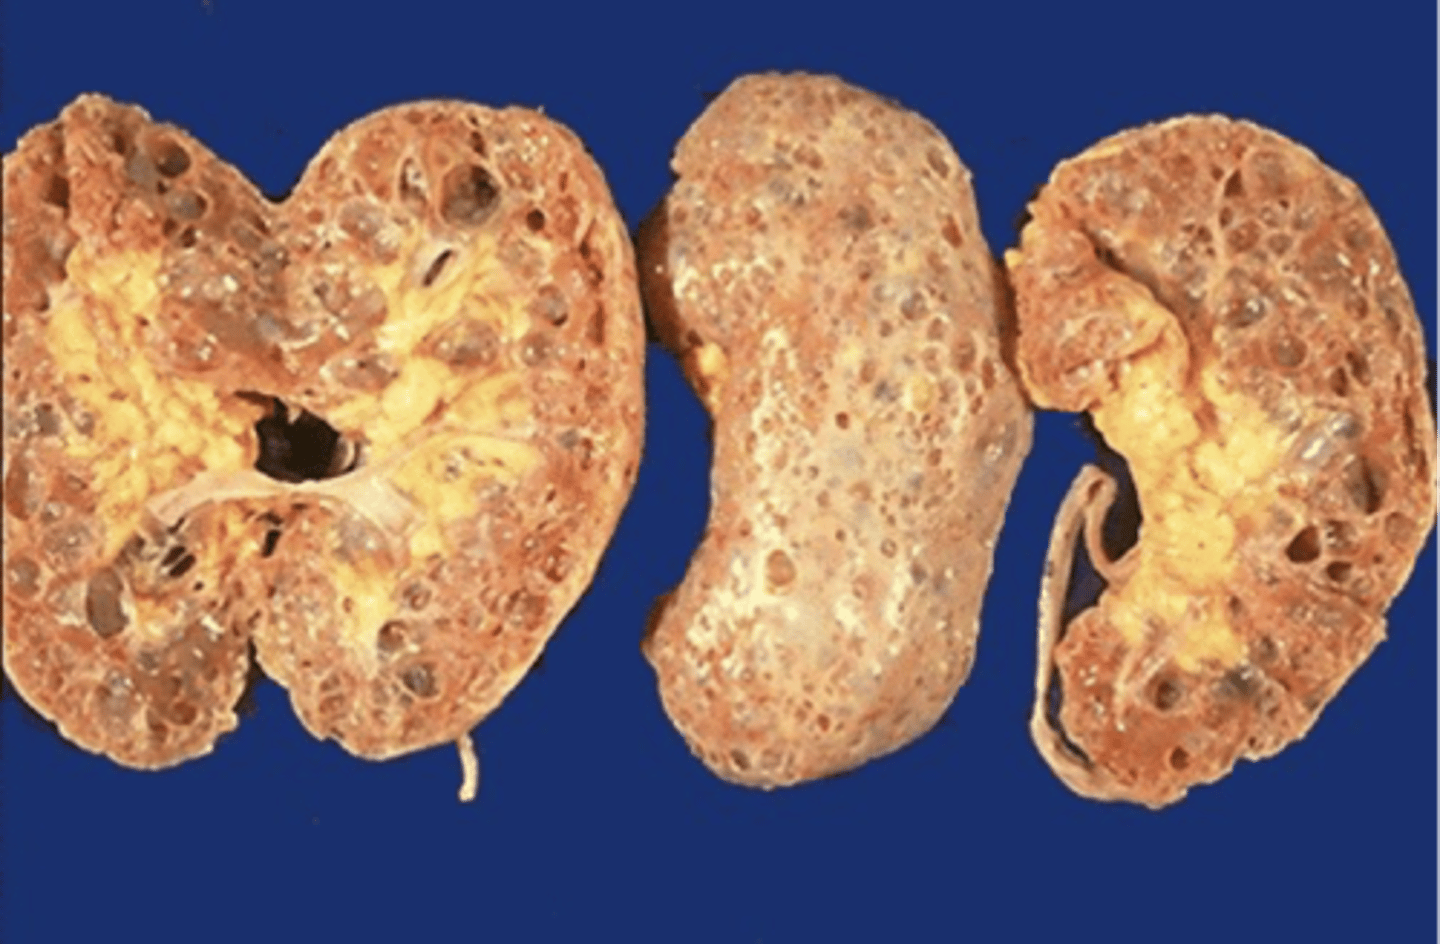

AD polycystic kidney disease

What disorder:

-85% of families have abnormality on chromosome 16 (PKD1 locus)

-remaining pts have abnormalities on chromosome 4 (PKD2 locus) --> less severe and often seen in late presenting

-Dx = imaging + Hx

-numerous cysts in cortex and medulla causing BL enlarged kidneys ultimately destroy kidney parenchyma

-Presentation = combo of flank pain, hematuria, HTN, urinary infection, calculi, progressive renal failure

autosomal dominant polycystic kidney disease

ID